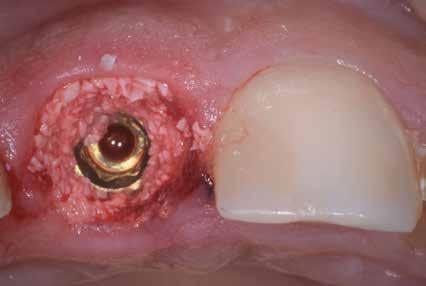

A 2020 januárjában elkezdett kezeléssorozat befejezését az év márciusában, hazánkba is begyűrűző Covid-19 pandémia késleltette, így kb. 6 hónap gyógyulás után láttunk hozzá az emergencia profil és a gingivális zenit ideiglenes koronával történő formázásához (11. és 12. kép). A 3 hetente végzett apró alakításokkal sikerült megfelelő ínyprofilt kialakítani, a „rózsaszín esztétika” a páciens számára is megfelelő volt. A bal felső nagymetsző fog meziális kompozit tömés cseréjét követően, individualizált nyitott kanalas lenyomati fejet készítettünk: az akrilát ideiglenes korona profilját átlátszó szilikonnal lemásoltuk, majd a körszimmetrikus gyári lenyomati fej és az ideiglenes korona kontúrja közötti hézagot folyékony kompozittal töltöttük ki (13. kép). Az így készített egyéni lenyomati fejjel vettünk lenyomatot a végleges, kerámialeplezésű cirkónium-dioxid vázas, átmenő csavaros rögzítésű koronához. (A fogtechnikai munkát Nébl Péter fogtechnikusmester készítette.), (14., 15., 16 és 17. képek).

A kész korona átadásakor a páciens elégedett volt az esztétikával, az azóta eltelt évben rendszeres kontrollokon jelent meg, melyek során meggyőződtünk a kemény- és lágyszövetek stabilitásáról (18. és 19. képek).